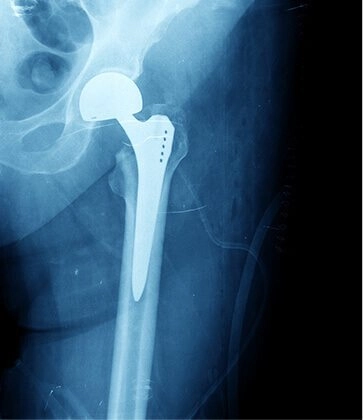

Total hip joint replacement surgery is a common solution for those dealing with conditions like hip fractures, dislocations, arthritis, labral tears, and hip impingement. The hip, a vital ball-and-socket joint facilitating lower limb movement, is frequently replaced due to factors like aging, wear and tear, overuse, injury, osteoarthritis, and falls.

The hip joint consists of the thigh bone's ball (femur) joining the pelvic socket (acetabulum), both lined with cartilage to prevent bone-on-bone friction. Damage to any hip joint component leads to chronic pain, discomfort, and limited mobility.

During a total hip replacement, the surgeon replaces both the femur and acetabulum with artificial parts, effectively relieving pain and enhancing mobility and function after the procedure, making hip replacement surgery a transformative solution.